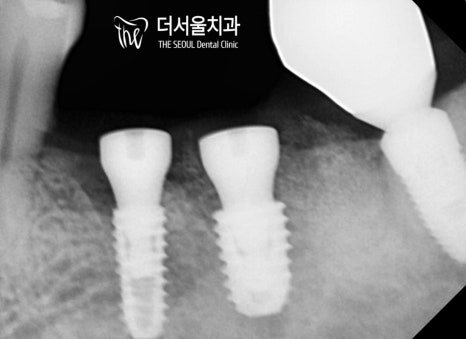

미리 결정된 식립 위치에 맞춰

컴퓨터분석임플란트 식립을 마무리 했습니다.

오늘도 해내는 더서울.. (짝짝짝)

가지런하게, 그리고 예쁘게 심어드렸습니다.

emergency profile도 딱 알맞게 형성되어 있는 모습이네요.

오래오래 보철을 사용하실 수 있도록

주의사항 및 관리법을 다시 한 번 강조드렸습니다.